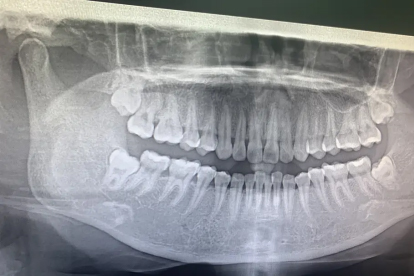

如果智齿与神经管距离较远,或虽然邻近但未引起明显不适,且通过影像学检查评估拔除风险较低,通常可以考虑拔除。此时智齿可能完全埋在颌骨内,或者只有部分萌出,但未压迫神经,患者可能没有疼痛或肿胀等症状。医生会通过锥形束CT等检查精确测量神经与牙根的距离,若距离安全,可采用微创拔牙技术,如切开牙龈、去除部分骨质后轻柔取出智齿,以降低神经损伤风险。术后建议注意口腔卫生,避免感染。

如果智齿与下牙槽神经管紧密相邻,甚至牙根包裹神经,或已导致反复发炎、疼痛、邻牙损坏等情况,且拔除操作可能直接损伤神经,则通常不建议立即拔除。这种情况下,强行拔牙可能引起下唇或牙龈麻木等神经损伤症状。医生可能会优先考虑保守治疗,如定期观察、抗炎处理,或转诊至口腔颌面外科专家评估替代方案,如冠状切切除术等部分拔除方式,以保留神经功能。若必须拔除,需在手术中采用神经监测技术,并告知患者潜在风险。